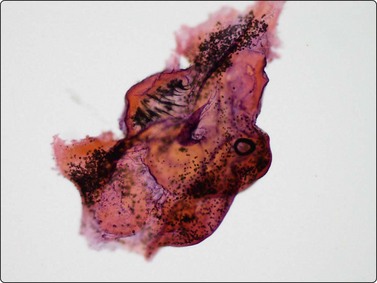

Fig. 18.20 (A) Hydatid scolex, showing hooklets and sucker (Pap, ×1000); (B) Hydatid laminated membrane. (C) Hooklet (Pap, ×400).

image

Fig. 18.21 Cysticercosis

Intact larva including scolex with hooklets (sickle shaped) and attached wall fragment (HE, ×200).

(Courtesy Dr Harsh Mohan, Chandigash, India)